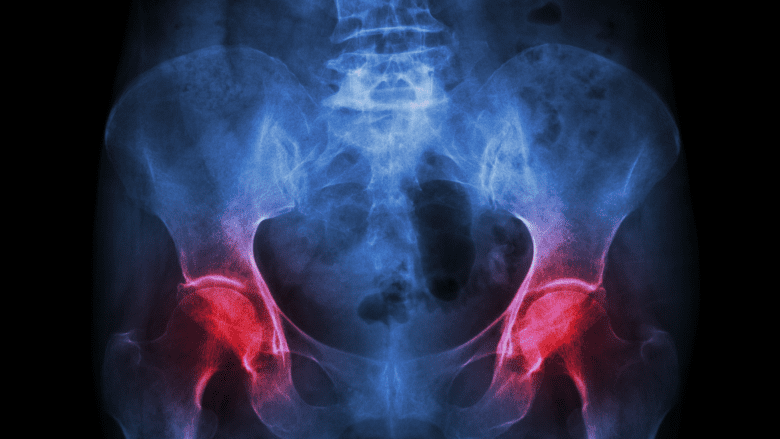

Pain from polymyalgia rheumatica often affects both sides of the hips or shoulders at once.

- Symmetrical joint pain is commonly seen in PMR affecting both the right and left sides (for example, both shoulders or both hips).